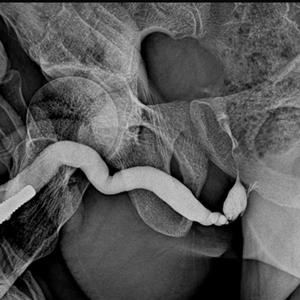

RGU :: RETROGRADE URETHROGRAM

IT IS DYE STUDY OF WHOLE URETHRA IN 2 TO 3 LIVE X.RAYS